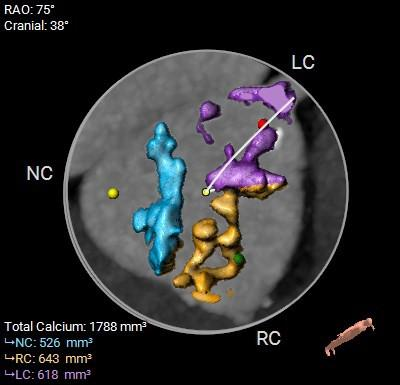

术前CT评估

1.CT数据显示该患者Type 1型二叶式主动脉瓣,左右钙化融合,瓣叶重度钙化并增厚,钙化分布较均匀,主要分布在无冠侧瓣叶边缘及左右交界。

2.主动脉瓣瓣环周长95.7mm,平均周长径30.5mm。

钙化分布